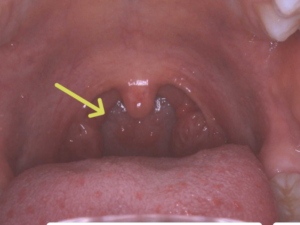

下の写真の→の部分が見えれば大丈夫です。

咽頭後壁(のどの奥)の写真を専用のカメラを使って撮影し、AIがインフルエンザかどうか判定するという新しい検査機器です。お口を大きく開けるだけでそれほど奥まで入れなくても大丈夫なので、痛みや不快感はほとんどありません。

AIが正確に診断するためには、のどの奥(咽頭)の画像が不可欠です。